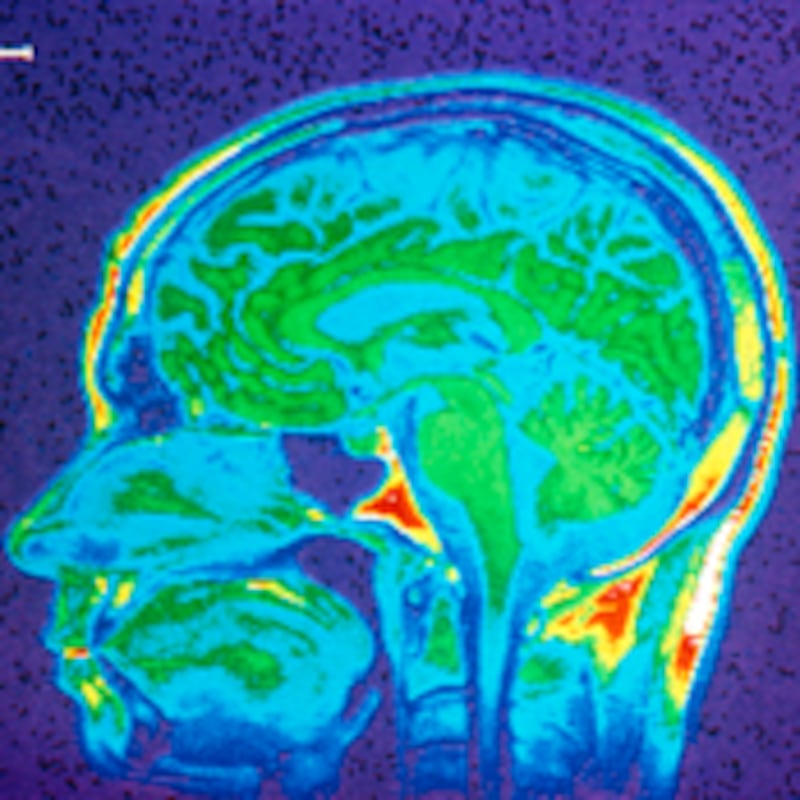

In 1991, a new technology was introduced that has since begun to demystify the brain: fMRI, or functional magnetic resonance imaging, which allows neuroscience researchers to illustrate the brain’s instant reactions and leaps of logic. You may be familiar with the images created by fMRI technology—depictions of the brain featuring gorgeous neon blobs on an otherwise grayish backdrop. These blobs (and yes, scientists actually call them that) represent areas in the brain that are activated by a given condition, such as seeing a snake, flames, or an angry human face. Today, the results of such fMRI experiments are giving researchers new insight into disorders as varied as overeating, autism, and anxiety.

During an fMRI study, a subject lies down in the middle of a giant magnetic tube. Once in the tube, they are presented with whatever task or stimulus the researcher has come up with, usually on a screen of some kind. While the subject is occupied, the fMRI machine makes a lot of noise and grabs hundreds of split-second portraits of blood flowing through the brain. This data is then subjected to layers of statistical analyses, the results of which are turned into those spectacular blob pictures.

The fMRI has done away with the need for cracked-open skulls. Instead, it harnesses the brain’s natural functions. Specificically, when any part of the brain is spurred into a state of increased activity, it needs oxygen, which is promptly delivered via the bloodstream. During an fMRI experiment, as the active brain neurons grab up that oxygen, they leave behind deoxygenated blood, which has a magnetic force. What the fMRI machine detects is the shifting proportions of oxygenated blood in any given region of the brain. This shift is considered the direct result of a shift in brain activity.